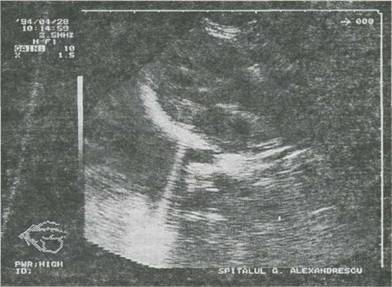

Fig. 9-11. Tetralogie Fallot. Echocardiografie 2-D, sectiune ax lung parasternal. Defect septai ventricular nerestrictiv īn partea membranoasa a septuiui, aorta "calare" pe septul ventricular, hipertrofie importanta ventriculara dreapta.